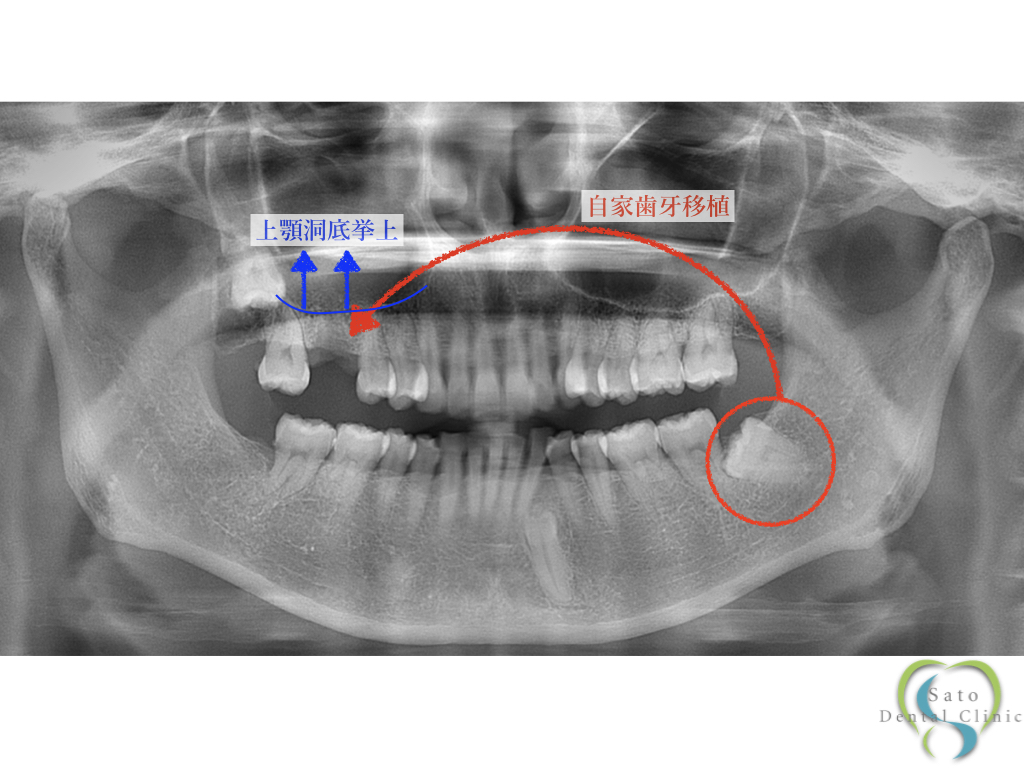

本症例では、左下に移植に適した形をした親知らず(単根歯)があったため、

患者さまと相談の上、この親知らずを右上欠損部に自家歯牙移植をすることとなりました。

右上の歯槽骨の高さがやや不足していたため、移植と同時に上顎洞底挙上術も併用する計画を立てました。

移植床の形成と上顎洞底挙上術を行なった後、左下の親知らずを取り出して、右上欠損部に移植・固定を行いました。